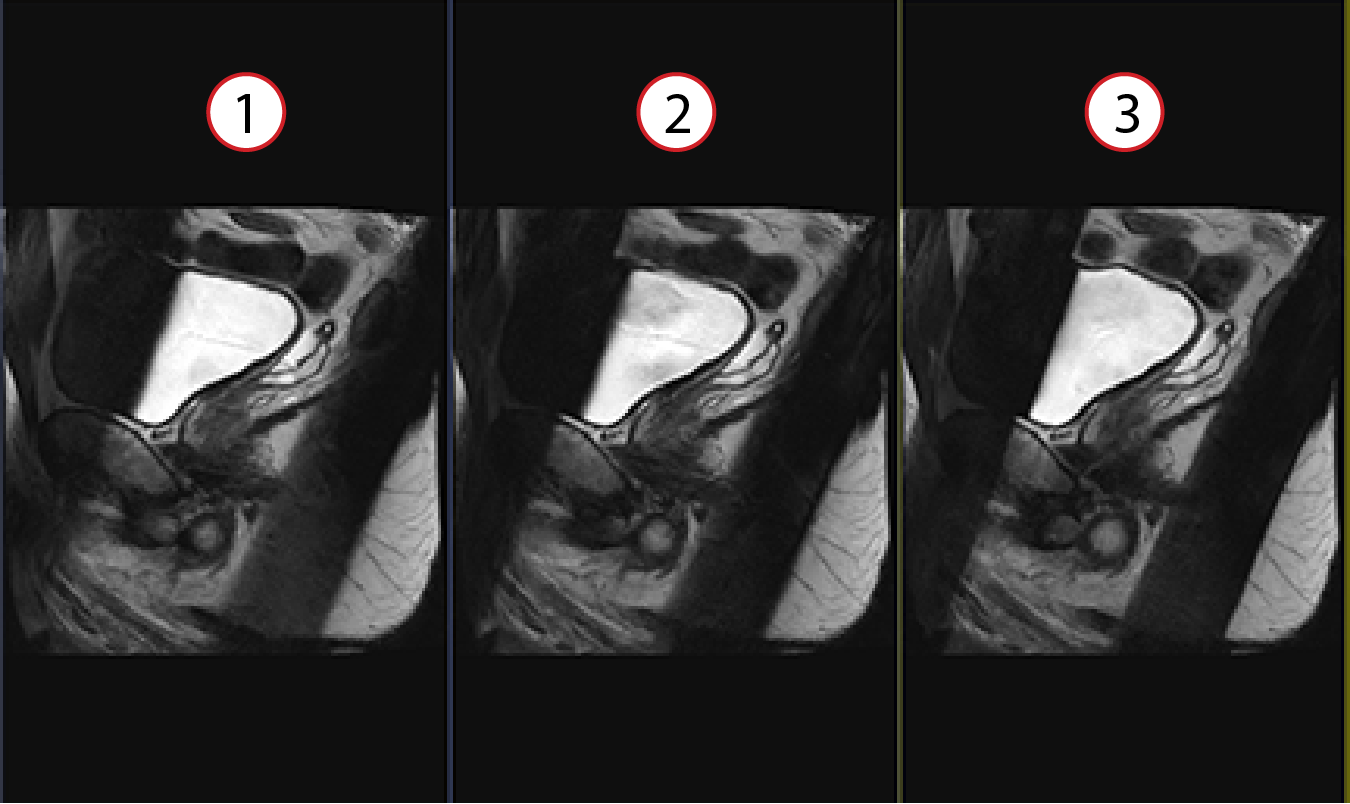

Figure 1. Spatial SAT Type applied to 2D FRFSE

Note: This example shows Spatial SAT applied anterior and posterior to the prostate.

Table 1. Image legend

ItemDescription

1Spatial SAT Type Light (0)

2Spatial SAT Type Medium (1)

3Spatial SAT Type Strong (2)